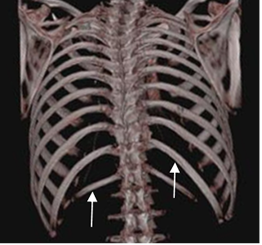

Fig 2. Costillas normales.

TAC reconstrucción 3D. Costillas flotantes, que no se unen al esternón.